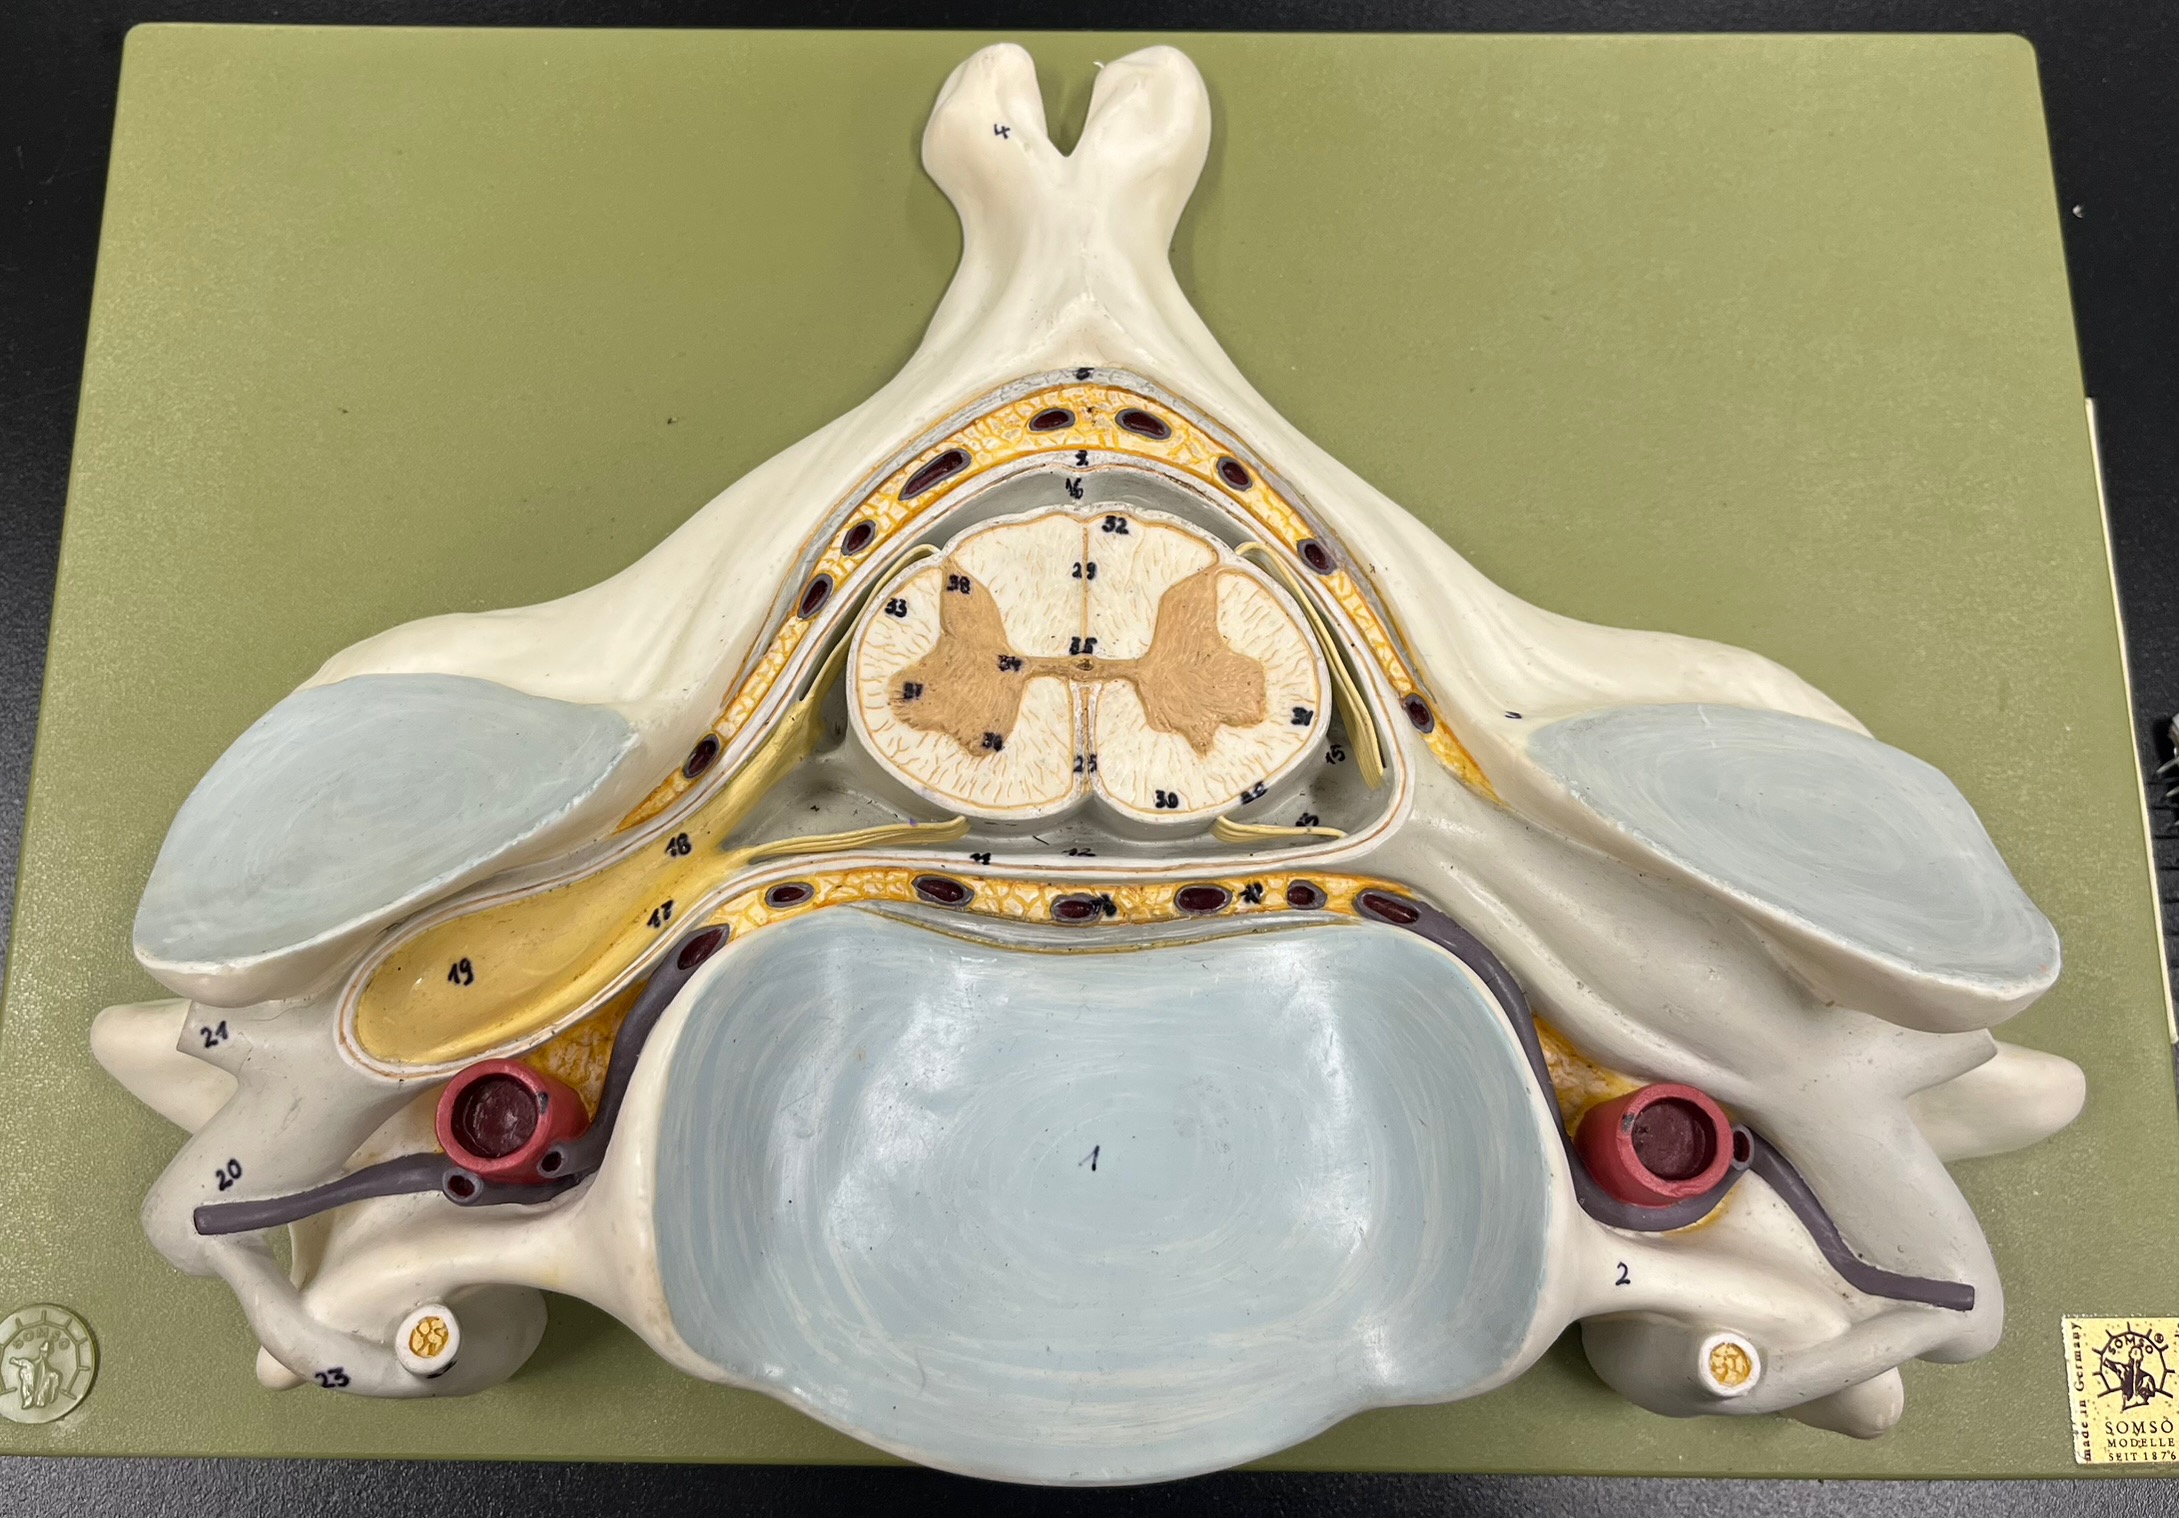

epidural space

dura mater

subdural space

arachnoid mater

subarachnoid space

pia mater

denticulate ligaments

anterior median fissure

posterior median sulcus

posterior (dorsal) horn

anterior (ventral) horn

lateral horn (selected models)

gray commissure

central canal

anterior column

lateral column

posterior column

white commissure

posterior (dorsal) root ganglion

posterior (dorsal) root ganglion

posterior (dorsal) root

posterior (dorsal) root

anterior (ventral) root

anterior (ventral) root

dorsal ramus

dorsal ramus

ventral ramus

ventral ramus

rami communicantes

rami communicantes

sympathetic chain ganglia

sympathetic chain ganglia